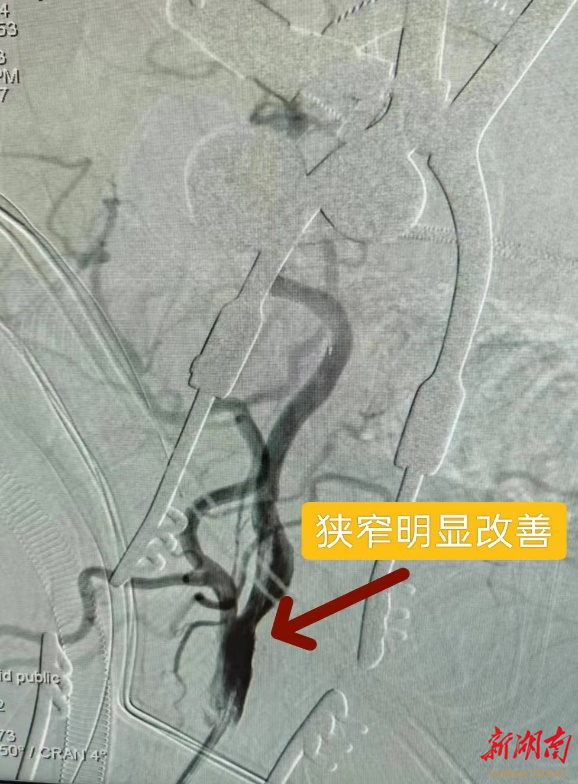

植入支架术后狭窄得到明显改善

术前造影提示左侧颈内动脉起始部重度狭窄